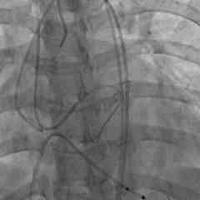

82岁老年女性,胸12椎体骨折。行球囊扩

82岁老年女性,胸12椎体骨折。行球囊扩张椎体成型术...

支架撑开并保留的椎体成型

支架撑开并保留的椎体成型...